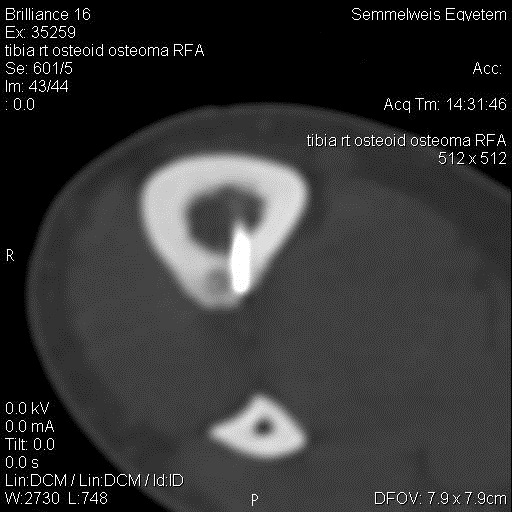

RF ablation is especially useful technique and has a good outcome in the direct treatment of osteoid osteomas (figure 20.) The invasiveness of the method is several folds smaller than orthopedic surgery.

Image

A

B

Figure 20. – RFA treatment of osteoid osteoma in the right tibia (A: CT exam before the treatment, B: RFA)

Patients treated with RFA only require 1-2 days of hospitalization as opposed to the ones undergoing open surgery, who need to stay in the hospital for 7-10 days.